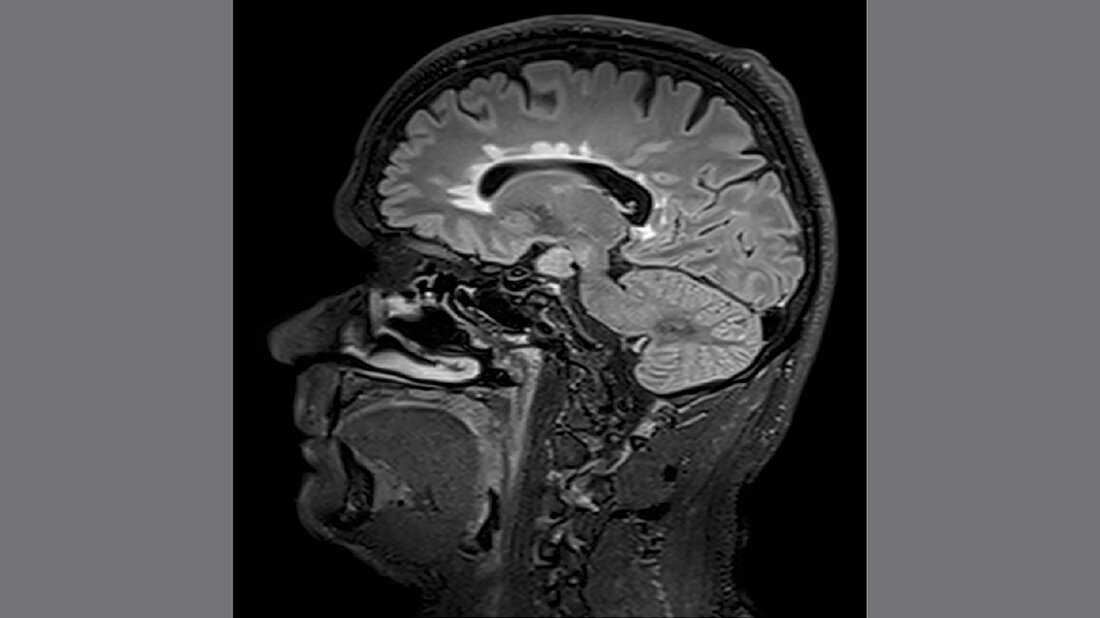

Basis ist die Erkenntnis, dass auch bei scheinbar stabilen Patientinnen und Patienten stumme Entzündungen entwickeln können. Entzündliche Läsionen im Gehirn können mithilfe der MRT nachgewiesen werden und erlauben eine Einschätzung des Krankheitsverlaufs auch bei geringer Krankheitsaktivität. Eine retrospektive Studie lieferte hier nun die wissenschaftliche Grundlage für neue Kriterien, die Therapie zu intensivieren bei scheinbar stabilen Patienten.

Denn die Läsionen sind häufig schon vor klinischen Symptome in der MRT sichtbar. In der Studie führte man bei 131 Patientinnen und Patienten, die mit einer gering- bis moderat-effektiven Immuntherapie für 12 Monate klinisch stabil waren, eine MRT durch. Die Ergebnisse zeigen, dass Patientinnen und Patienten mit zwei oder mehr Läsionen innerhalb eines Jahres von dem Wechsel auf eine hoch-effektive Immuntherapie profitieren – auch wenn sie klinisch noch keine weiteren Symptome zeigten.

Studienleiter Harald Hegen betont: „Nachdem Läsionen oft schon vor dem Auftreten klinischer Symptome in der MRT sichtbar sind, ermöglicht eine bildgebende Kontrolle bei Patient:innen mit einer gering- bis moderat-effektiven Therapie ein frühes Eingreifen in den individuellen Krankheitsverlauf.“ Die bisherige klinische Praxis besagt eine Therapieverstärkung erst nach dem Auftreten klinischer Symptome. Die Studie zeigte jedoch, dass 40 Prozent der Patientinnen und Patienten klinisch stabil waren, im MRT jedoch schon Läsionen aufwiesen.